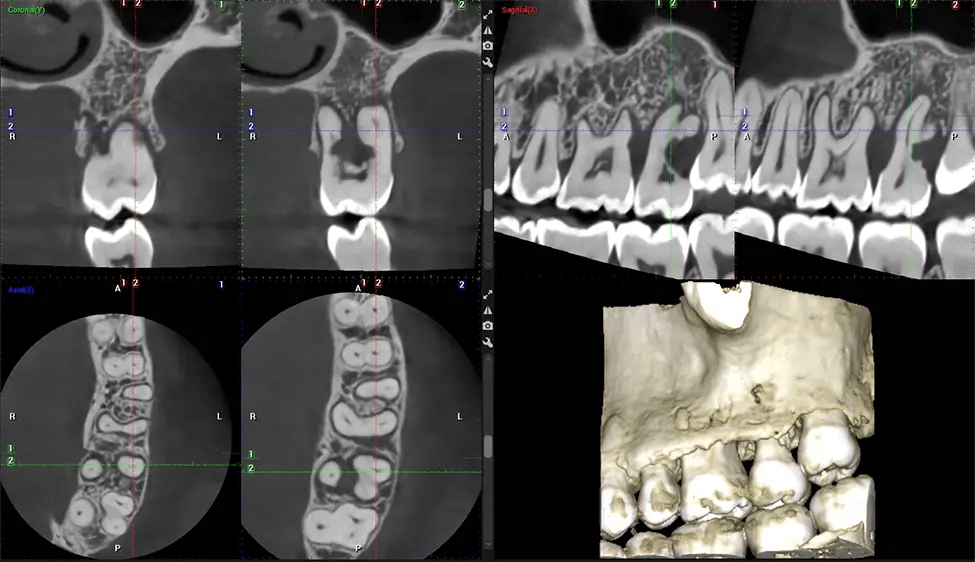

This 3D scan, called cone beam computed tomography, gives your dentist a more complete image of your oral anatomy and disease processes than a traditional X-ray. Unlike conventional X-rays, which capture a 2D image of your mouth from various angles, a 3D scan takes multiple digital X-rays for one image. It provides a complete view of your jaw, teeth, nerves, and soft tissues. This enhanced view allows dentists to detect minor issues not visible in traditional 2D scans, such as impacted wisdom teeth or bone fractures in the sinus cavity.

There are many benefits to using CBCT technology, especially compared to the traditional 2D X-ray format. One of the most significant advantages of CBCT scans is that they provide much more information than traditional X-rays. A scan lets your dentist see images from all angles of your jaw and mouth, including your sinuses, nasal cavity, cheekbones, and other surrounding areas. This added information helps your dentist craft a comprehensive treatment plan that addresses all aspects of your oral health.

Another significant benefit is that 3D imaging provides more precise images of your bone structure. These images are more detailed, providing you with a more accurate diagnosis. An accurate diagnosis means better treatment for you.